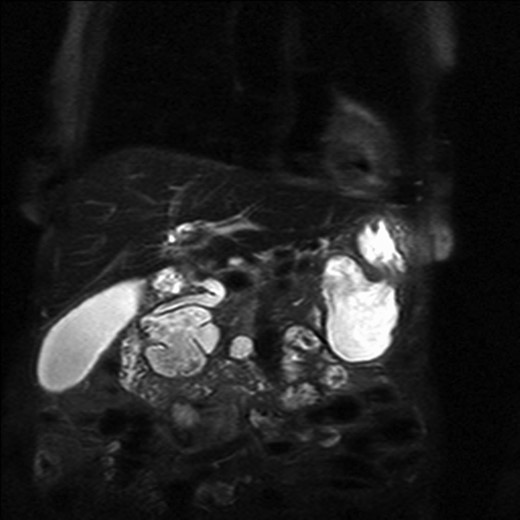

The patient underwent an MRCP which demonstrated mild distension of the gallbladder with several calculi. There was intra- and extra-hepatic biliary dilatation to the level of the ampulla. A very large fluid and air filled periampullary duodenal diverticulum measuring ~8 cm in the long axis was also noted (Figs 1–3). This finding was unchanged compared to a CT study from 6 months previously. The CBD was dilated to the level of this diverticulum and the cause of the patient’s biliary dilatation and obstruction. Interestingly, an unusual appearance to the kidneys was recorded with multiple microcystic changes in both kidneys, which is typically reported in patients with lithium induced renal disease. A gastroduodenoscopy revealed a large periduodenal diverticulum in D2 (Fig. 4).